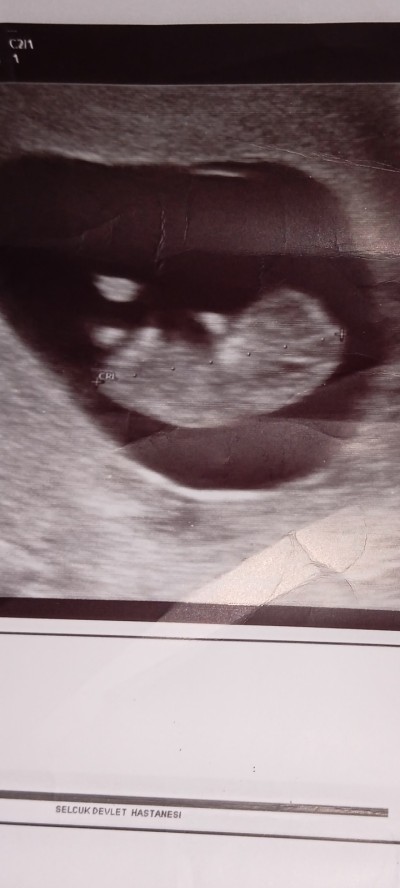

Cinsiyet tahmini yapabilen var mı ?

Gebelik haftası 11

Valla canım sen bebeği yandan resmini atmışsın doktorlar bile bu pozisyonda göremiyor biz nasıl görüp söyleyelim bacak arasının resmini çekmesi lazımdı doktorun sağlıklı olsun inşallah ama ben pek birşey hissedemedim

Valla canım erkek olabilir çünkü benim oğlumda bu şekilde toplu duruyordu ve erkek bebeklerinin karnı çabuk çıkıyor ve dik şekilde oluyor sivri gibi oluyor benimkini öyle erkek dediler gerçekten erkek çıktı kız çocuğu uzunlamasına duruyor kızım var bu da erkek oğlumda toplu duruyor rabbim gonlune göre versin hayırlı evlat olsunlar sagliklo olsunlar doktora gitsen belki görür burada senin haftanda görenler var